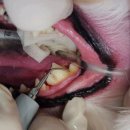

• 목동찬동물의료센터 | 내돈내산 | 고양이 구내염 치주염 치석에 좋은 고양이 치약, 칫솔 추천!

약 먹이는 것 처음 해봤는데 .. 저 생각보다 잘 먹이는 것 가타욤 ㅎㅎ .. (걱정했는데 .. 야호 돈 굳었당 헷 ..) ​ 한 번에 쑈옥- ✌️😘 ​ 병원은 요기!! ​ 목동찬동물의료센터 서울특별시 양천구 오목로 285 1층 그래서 바아로!! ​ 가장~ 유명하고~ ​ 이미 별밭이 형님인 레오 형님이 사용하고 있는 오라틴 메인터넌스 투...

느리지만 행복하게 ෆ(2025-10-31 22:45:00)